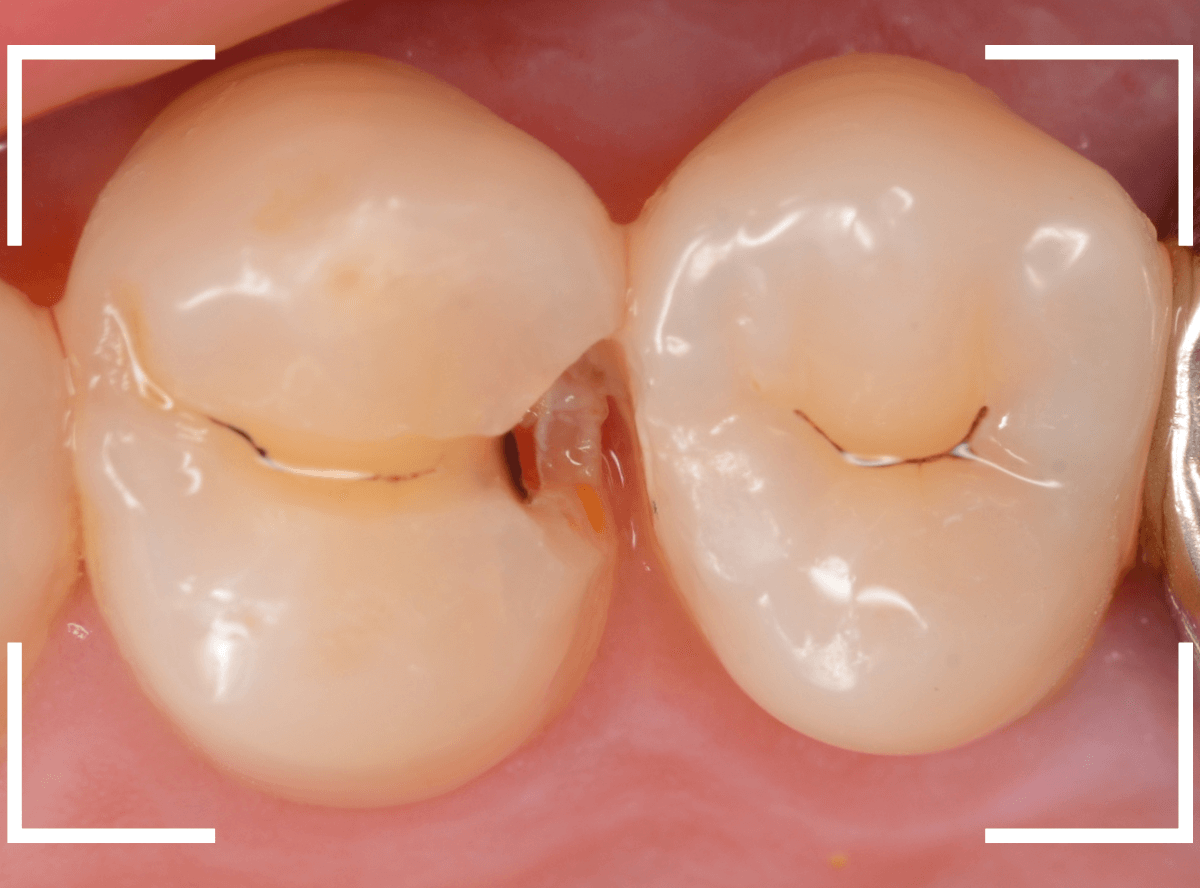

Case.13 問題なさそうなレジンの下で深い虫歯

他の歯の治療希望で来院された患者さんで、レントゲンで大きな虫歯が見つかった方です。

以前に虫歯を削って、レジンをつめる治療がしてあります。

表面を見る限り、特に問題はなさそうです。

両歯とも、色々嫌な予感のする所見です。